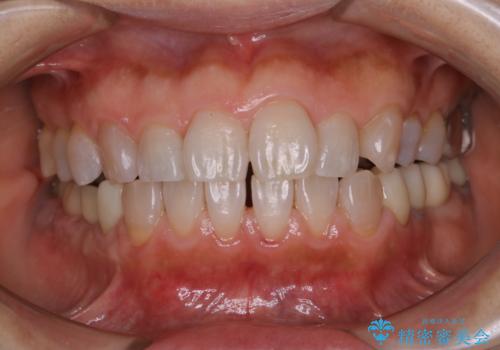

口臭予防のため歯科医院での歯の掃除 PMTC

- 口臭予防のためクリーニングをしたいとのことで来院されました。PMTC60分コースを行いました。

PMTC(自費クリーニング)60分コースを行いました。

PMTCで、バイオフィルム(細菌の塊)を破壊し、歯の表面をツルツルにすることでお口の中の細菌数を減らし歯周病のリスクが定着するのを防ぎます。更に、歯に新しい汚れがつきにくい状態になります。

バイオフィルムが除去されると、ご自身本来の歯の表面になります。PMTCをすることで口臭予防にもなり、定期的に行うことが大切です。